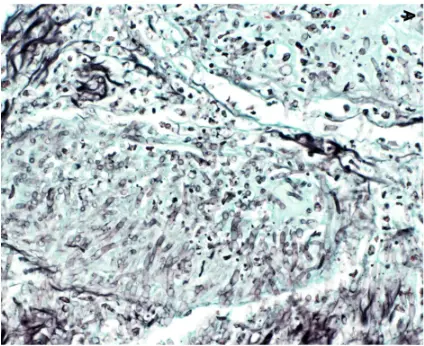

PASM-Masson staining plays a pivotal role in renal pathology by specifically visualizing the glomerular basement membrane and extracellular matrix. This capability allows for precise assessment of renal tissue architecture, particularly the delicate structures essential for kidney function. The staining method helps to emphasize the basement membrane’s presence and state so pathologists can identify any irregularities that could affect filtration processes effectively and accurately visualizing these structures assists, in spotting diseases and determining the right treatment approaches.

renal

Identification of Basement Membrane Alterations

Changes in the basement membrane may suggest kidney issues and the use of PAS Masson staining is effective in spotting these alterations.PATHOLOGISTS depend on this method for recognizing thickening or thinning as well as breakages in the basement membrane that can signal problems, like glomerulonephritis or diabetic kidney disease.  By pointing out structural deviations, PASM-Masson staining contributes to an accurate differential diagnosis and can inform prognostic evaluations.